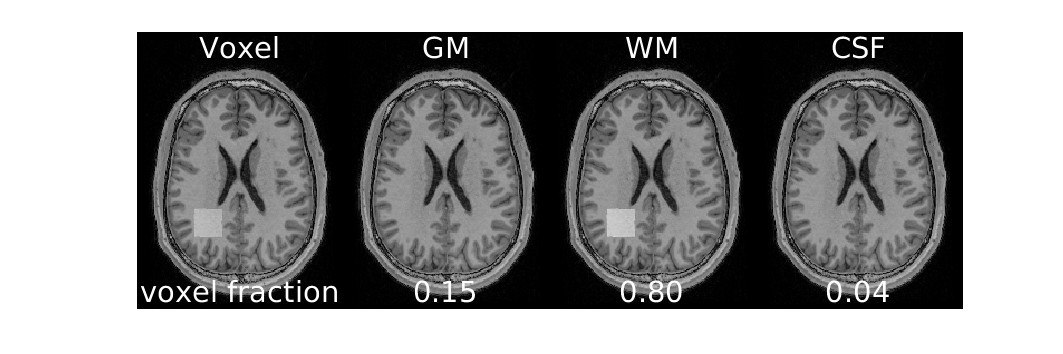

Osprey performs alignment with T1

Osprey also performs segmentation to determine the proportion of tissue types within the voxel (for WM and CSF correction)

display(ipython_image(filename=f"{output_path}/Reports/reportFigures/sub-002/sub-002_seg_svs_space-scanner_mask.jpg"))